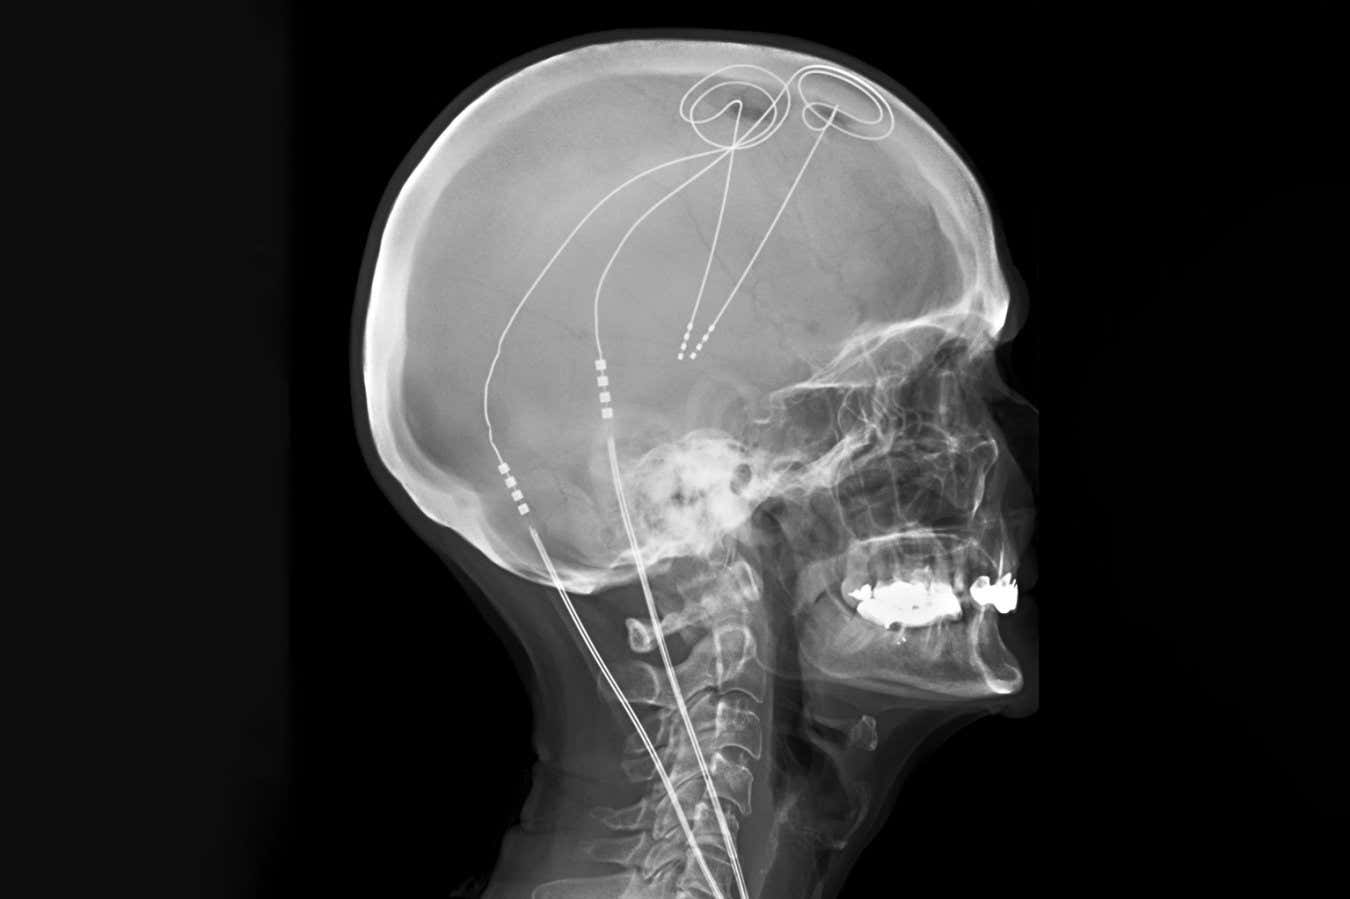

Bu yüzden Kaliforniya Üniversitesi, San Francisco ve meslektaşları Prasad Shirvalkar, kişiselleştirilmiş bir sistemin daha etkili olup olmayacağını merak ettiler. Öğrenmek için, daha önce tedavi edilemeyen kronik ağrıya sahip altı kişiye, elektrotların 10 gün boyunca beyinlerinde 14 bölgeden aktivite kaydettiği ve bunları uyardığı intrakraniyal elektroensefalografi uygulandı.

Araştırmacılar daha sonra makine öğrenimini kullandılar, bireyler yüksek veya düşük düzeyde ağrı yaşadığında meydana gelen elektriksel aktiviteyi tanımlamak ve ayırt ettiler. Daha sonra, beyin aktivitelerini izlemek ve ağrı ile ilgili aktivite tespit edildiğinde optimal stimülasyon sağlamak ve uyurken deaktive etmek için kişiselleştirilen her katılımcıya kalıcı DBS elektrotlarını implante ettiler.